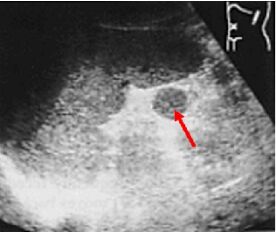

63.右上腹部超音波掃描時,發現一囊狀構造橫徑超過4公分,壁厚超過3公釐,內有高回音結構且具有 後側音影(acoustic shadowing),以及陽性超音波墨菲氏徵象(positive sonographic Murphy's sign),下圖最有可能的診斷為何? (A)急性結石性膽囊炎(acute calculous cholecystitis) (B)急性無結石性膽囊炎(acute acalculous cholecystitis) (C)急性氣腫性膽囊炎(acute emphysematous cholecystitis) (D)膽結石性腸阻塞(gallstone ileus)